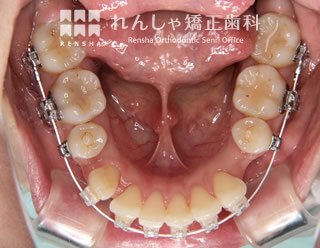

過蓋咬合(14歳 治療期間:2年8か月)

正中離開(前歯の間にあいた隙間)が気になり来院されましたが、過蓋咬合(深い噛み合わせ)が主な原因になっていることがあきらかでした。

下歯列形態は左右非対称になり、右奥歯の噛み合わせがすれ違っています(鋏状咬合)。この噛み合わせを放置すると、上前歯の前突やすきっ歯はさらに悪化し、右奥歯は全く噛めなくなってしまいます。

まず過蓋咬合と右奥歯の噛み合わせを改善し、その後上前歯を後退させました。

| 主訴 | 前歯の隙間と歯ぎしり |

| 診断名 | Angle Class II 過蓋咬合を伴う上顎前突 |

| 初診時年齢 | 14歳5か月 |

| 装置名 | マルチブラケット装置 |

| 抜歯非抜歯 | 上顎両側第一小臼歯(合計2本) |

| 治療期間 | 2年8か月 |

| 費用の目安 | 約89万円+消費税(検査料金、都度の処置費用等も合わせた総額) |

| リスク副作用 | 歯の移動に伴う軽微な歯根吸収、歯槽骨吸収、歯肉退縮(いずれも本症例ではほぼ無し)、矯正器具装着中のカリエスリスク増大(本症例ではカリエス発生無し) |